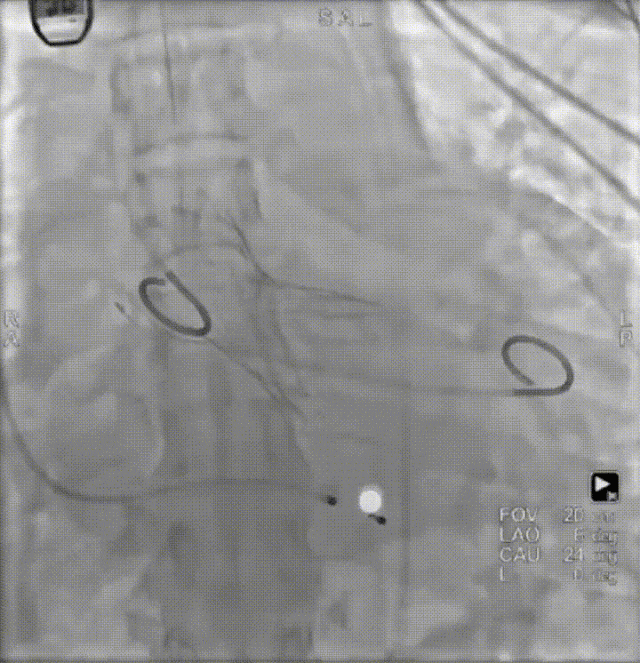

病例概览

患者病史 男性,74y, 因 “发现心脏瓣膜病 1 年,加重伴喘气半年” 入院。门诊检查显示主动脉瓣重度AS并伴轻-中度AR。患者基础疾病较多:胸腹主动脉多发穿透性溃疡、心功能III级等,手术指征明确,但风险极高。 术前CT LVOT- Annulus 倒梯形,对植入瓣膜有挤压位移风险,Annulus直径23.7mm,瓣叶增厚,钙化集中在无冠窦边缘。 左冠脉开口高度可,瓣叶不长、窦部空间较大,无冠脉风险;室间隔膜部较短,有一定PPI风险,心脏角度37.9°;心室较小,有一定循环崩溃风险,术前注意补液。 术前造影角度及入路:血管入路散在钙化、无迂曲;主动脉弓条件好、双侧股动脉直径大、右股穿刺点侧壁存在环形钙化 左右重合位:RAO 7° CAU 21° 右窦中心位:LAO2 1° CAU 1° 手术策略 20mm球囊预扩后植入AV26瓣膜,同时做好预防循环崩溃、传导阻滞的应急预案。 术中挑战 1)球囊预扩:20mm球囊预扩时无明显 “腰征”,但存在少量反流,提示瓣膜钙化与解剖结构对扩张的阻力不均 2)首次释放偏差:第一次定位释放时,瓣膜在 “开花” 过程中下滑约 3mm,工作位观察显示小弯侧瓣周漏较多(深度超过完全覆膜区),需二次调整。 3)二次精准定位:以猪尾导管为参照,将定位点调整至 “猪尾 - 2mm” 处,结合真实窦底深度(较深)重新释放,最终瓣膜位置稳定,瓣周漏显著减少。 术后即刻效果: 瓣膜形态良好,跨瓣压差从术前的 67mmHg 降至 6mmHg,且无明显瓣周漏,冠脉开口通畅; Commisural Alignment 术后即刻超声: Prostyle A®预装干瓣——助力临床最优化解决方案: √ 平衡的径向支撑力:特殊的解剖结构下位置形态良好,术后跨瓣压差大幅降低,血流动力学改善明显; √ 80%可回收设计:支持术中二次调整释放位置,保证精准释放; √ 平衡的收腰设计&Commissural Alignment设计: 为患者后期冠脉PCI保留了生命通道;